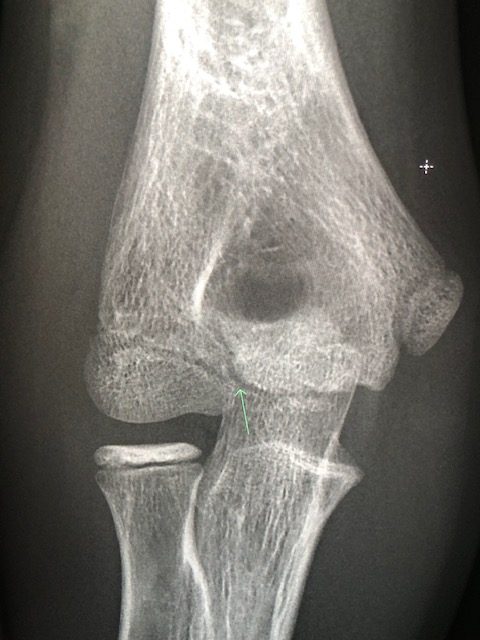

Fracture or not Leave a Comment / Cases / By OCAD Hi everyone 13 yr old male , hit with an ore. Would you call this a fracture ? Foroogh